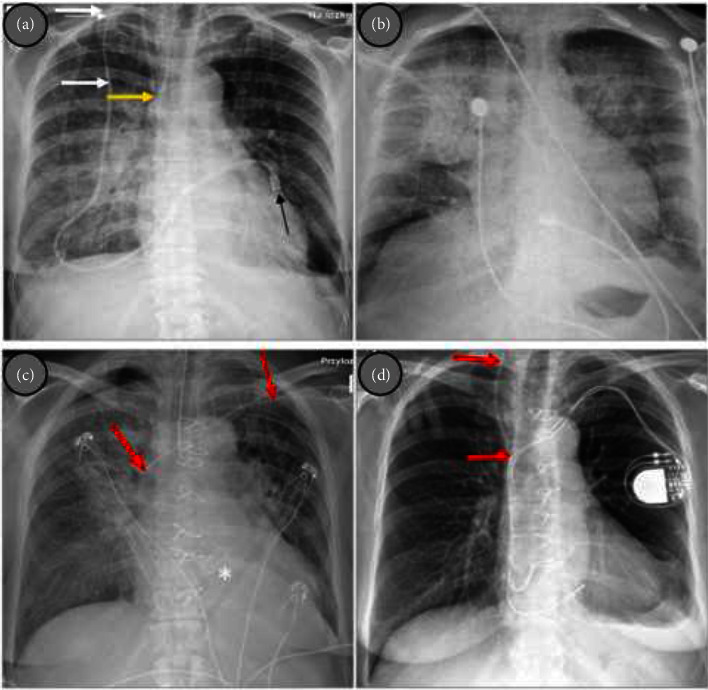

Introduction: Broviac catheter is a type of central venous catheter (CVC) used for long-term parenteral nutrition in specific patients, e.g., diagnosed with intestinal failure as short bowel syndrome (SBS). The way of the catheter insertion is conceived to minimalize the risk of infections. However, CVC-related blood stream infections (CVC-BSIs), including infective endocarditis (IE), remain most important complications associated with Broviac catheter. Staphylococcus epidermidis stands out as a prevalent pathogen. The increasing number of CVCs results in an increased incidence of healthcare-associated IE. Complete parenteral treatment is an independent risk that increases the likelihood of IE. Treatment of IE is mainly based on antibiotic therapy, but in certain cases, surgical treatment is needed. Presentation of Case: A 71-year-old female with SBS who had been receiving total parenteral nutrition through the Broviac catheter for several months was admitted in a serious condition with significant weakness, increasing shortness of breath, deteriorating cough, fever, low blood pressure, and heart palpitations. Echocardiography revealed severe aortic valve IE with a large, longitudinal, highly mobile vegetation (up to 40 mm) and massive aortic regurgitation with pulmonary edema. Fast pathogen detection in the patients' blood (S. epidermidis) was obtained using PCR-based multiplex test. Due to life-threatening conditions, emergency surgery with aortic valve replacement was performed. Consistent rehabilitation resulted in good condition achievement. Follow-up echocardiography showed normal function of the aortic valve bioprosthesis. Conclusion: The use of CVC, including Broviac catheter, is associated with an increased risk of infections, including IE. Treatment-resistant severe HF complicating IE requires emergency surgery.